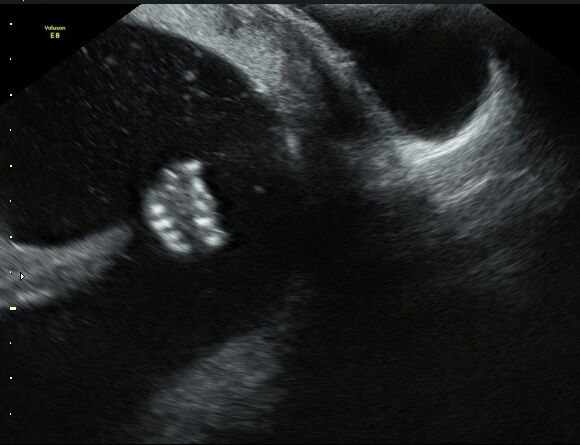

В общем, был минус, не захотел он нам показывать профиль ни в какую (не все замерили), отправила она меня чай пить с конфетами, через минут 15 все равно, ни в какую, зря мучили 🐣. Ну да ладно в 20 встретимся))) Опять показал нам писюн во всей красе и кулак из вредности, весь в папу блин, если нет, то нет 😘😹

🌼 из УЗИ - плацента по передней стенке... ((( пока низко, но рано судить..

🌼 все замеры в пределах нормы, на 16-17 недель, пока также на недельку отстаем от дпм.